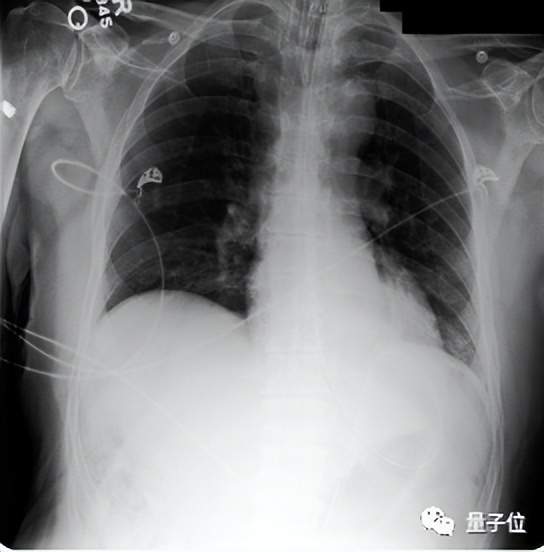

而在246份真實胸部X光片中,臨床醫(yī)生表示,在高達40.50%的病例中,Med-PaLM M生成的報告都要比專業(yè)放射科醫(yī)生的更受采納,這表明Med-PaLM M并非“紙上談兵”,用于臨床指日可待。

如下圖所示的胸部x光解讀和皮膚病變分類任務(wù)所示,這些指令有一種寫提示語的味道,以“你是一個很給力的放射科助理”開頭。

(3)零樣本思維鏈推理能力涌現(xiàn)。Med-PaLM M可以通過胸部X射線圖像檢測沒有訓練過的結(jié)核病,與針對該類數(shù)據(jù)集進行專門優(yōu)化過的SOTA結(jié)果相比,它的準確率已相差不大。

不過,它給出的具體報告還是存在具體錯誤,說明還有不足。

(4)放射性報告生成測試中,80B參數(shù)的Med-PaLM M平均有40.50%的報告比放射科醫(yī)生做的更好(被臨床醫(yī)生采納),而12B和562B,分別為34.05%和32.00%。

另外,遺漏和錯誤率測試顯示,Med-PaLM M 12B和84B模型平均每份報告的遺漏率最低,為0.12,其次是562B模型為0.13。這一結(jié)果與MIMIC-CXR上人類放射科醫(yī)生基線報告的相當。